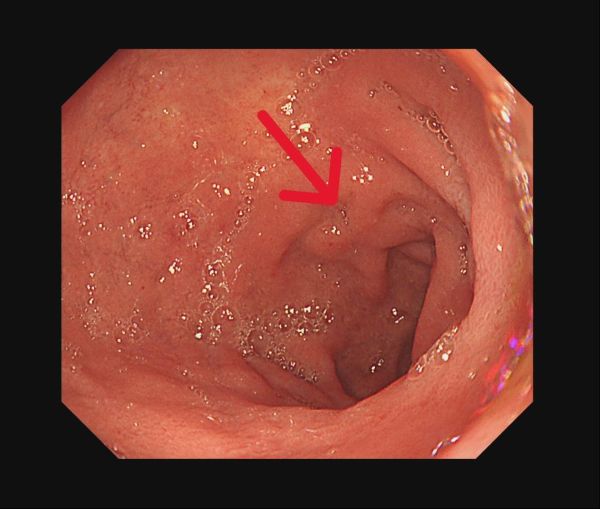

【記者吉雄世/高雄報導】53 歲男子因持續胃痛、食慾下降而日漸消瘦,至義大癌治療醫院血液腫瘤科饒坤銘副院長門診求診。原以為只是常見的腸胃不適,經檢查後,診斷第三期胃癌,腫瘤已明顯影響胃部功能,短短時間讓他體重減輕 10 公斤。突如其來的噩耗,讓病人與家屬瞬間陷入巨大的焦慮與無助。

過去胃癌治療多以手術後化療為主,但近年研究已證實,術前治療能有效提升腫瘤可切除率。若術後病理組織中「完全找不到癌細胞」,稱為「病理完全反應」,通常與更低的復發風險及更理想的長期預後相關,已成為國際高度重視的治療指標。

經義大醫療外科團隊進一步評估後,患者體況已達手術標準,並順利接受胃部腫瘤切除手術。手術後的病理報告更帶來令人振奮的結果:腫瘤組織中未發現殘存癌細胞,成功達成「病理完全反應」。得知結果的當下,患者與家屬喜極而泣,醫療團隊也深感欣慰,這不僅是治療上的成功,更是病人、家屬與醫療團隊共同努力的成果。